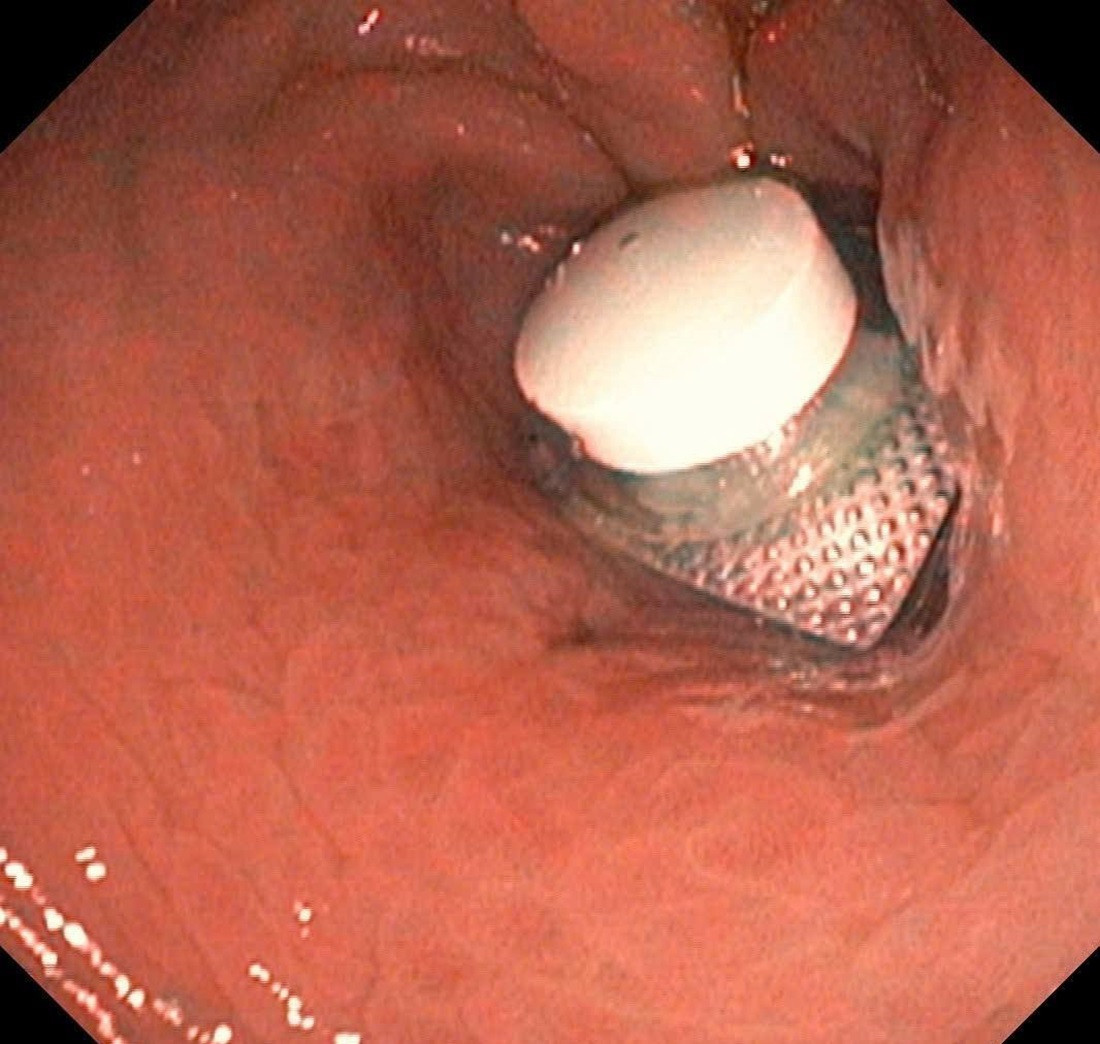

Trước đó, bệnh nhân nam 52 tuổi nhập viện cấp cứu trong tình trạng đau bụng dữ dội. Qua thăm khám lâm sàng, bệnh nhân được bác sĩ chỉ định nội soi dạ dày và phát hiện tại môn vị có dị vật là viên thuốc còn nguyên vỏ, gây trầy xước niêm mạc dạ dày.

Ngay sau đó, các bác sĩ đã tiến hành nội soi gắp dị vật và lấy ra thành công, đảm bảo an toàn cho người bệnh.